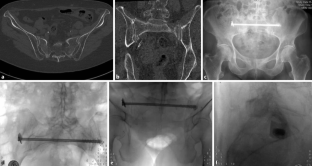

Abb. 3